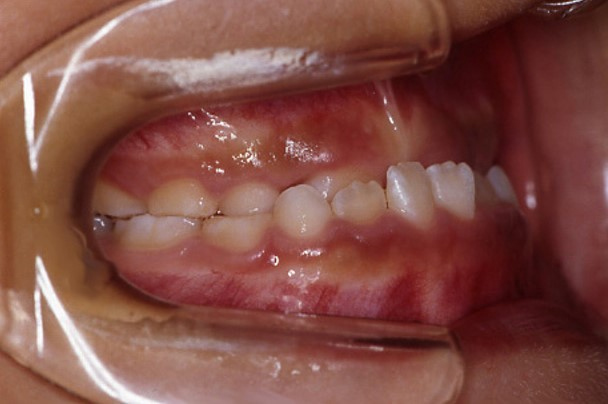

7歳3か月の男子

受け口を歯列矯正用咬合誘導装置「上顎前方牽引装置」で治療した症例

| 主訴 | 上下の前歯が反対咬み(受け口)になっていて、下あごがしゃくれている気がする。 |

| 診断名 | 骨格性反対咬合(こっかくせいはんたいこうごう) |

前歯のかみ合わせが反対になっていることと、横顔で下あごがしゃくれていることが気になって来院されました。

お父様が少し受け口でしたので、遺伝的にも受け口の傾向があると疑いました。検査をしたところ、上下の顎の位置が原因の「骨格性反対咬合」という状態であることがわかりました。「受け口」というと下あごが前に出ている様子を想像してしまいますが、この患者さんは上あごの成長が弱いタイプの受け口でした。この状態は放っておくと成長とともにさらに受け口がひどくなる可能性があることと、上あごの成長を用いる矯正治療は早いうちにしておかないと効果が出にくくなることから、すぐに矯正治療を開始しました。